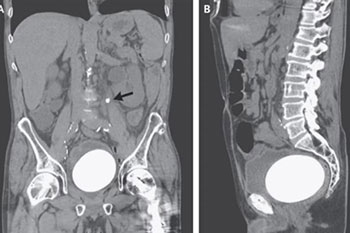

Pregled abdomena CT-om pokazao je nešto što dotad liječnici nisu vidjeli. Kamenac težine 770 grama, dimenzija 12 x 9,5 x 7,5 centimetara, veličine je nojeva jajeta. Prosječni kamenci koje pronađu u tijelima pacijenata teže oko 1,3 grama te ih je slučaj ovog muškarca itekako začudio.

Liječnici su za The New England Journal of Medicine otkrili kako se radi o muškarcu koji je desetak godina ranije imao invazivni rak mokraćnog mjehura. U to vrijeme morali su mu ukloniti mjehur i od dijela njegovih crijeva formirati novi, što za posljedicu ima povećani rizik od nastanka kamenca, piše Live science.

Muškarac je podvrgnut operaciji kako bi kirurzi izvadili veliki kamenac, dok su druge, manje, uklonili nakon laserskog razbijanja na manje dijelove.